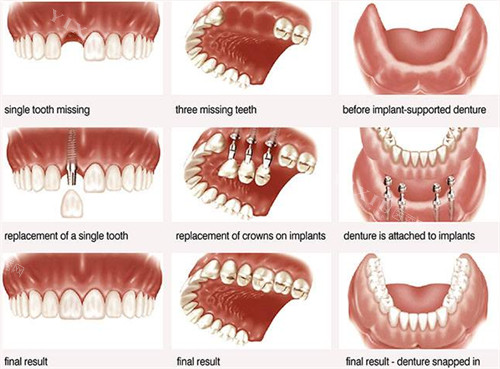

种植牙类价格

种植牙作为目前较为持久的缺牙修复方式,在瑞康综合牙科提供多个价位选择。基础款种植体配合普通牙冠的起步价约为5700元。中端种植系统如韩国登腾系列,单颗价格7200元起。对于追求更佳稳定性和长期改善的患者,可选择欧美进口种植系统,价格在7600元以上。值得注意的是,种植手术前需进行详细的口腔检查和评估,部分患者可能需要先要进行骨增量手术,这部分费用需额外计算。